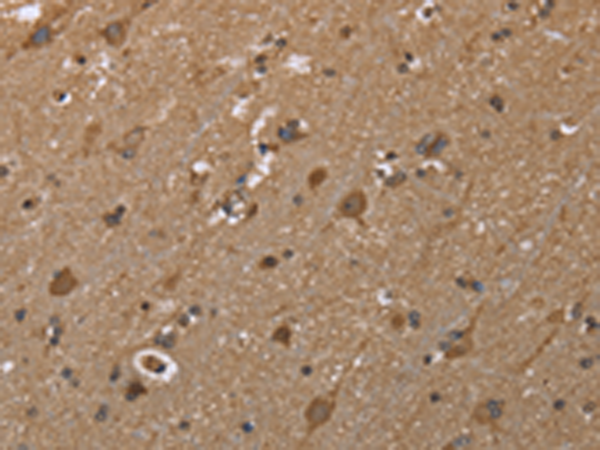

分类: 科研抗体货号: P01389别名: ALKBH9应用: WB,IHC反应种属: Human